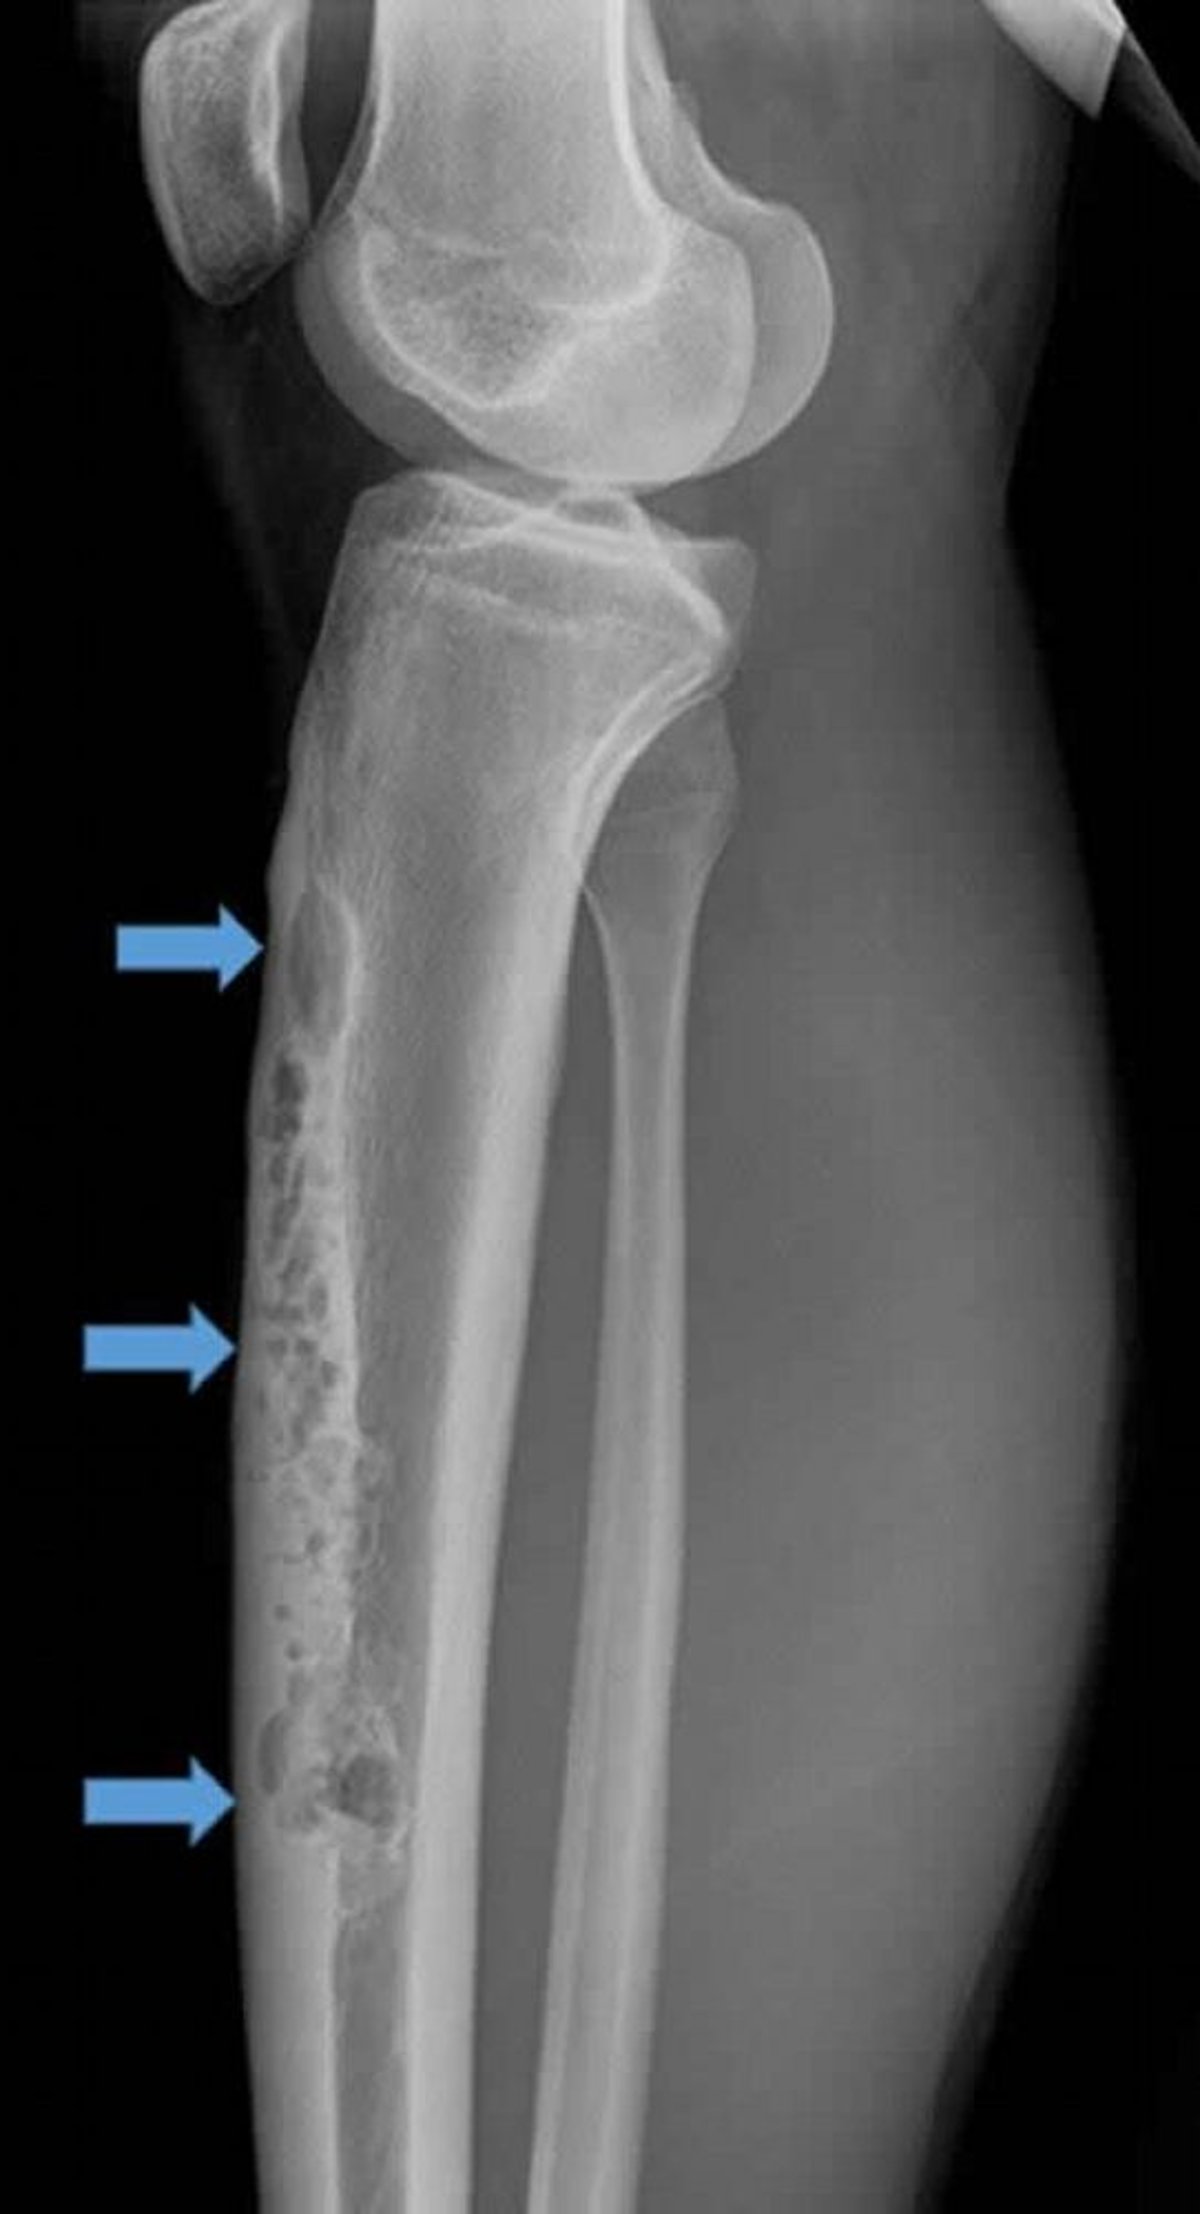

Adamantinome

Cette radiographie latérale du tibia droit montre un volumineux adamantinome intracortical antérieur (flèches). Noter l'aspect perméatif et ostéolytique en « bulles de savon ».

Image courtoisie de Michael J. Joyce, MD, and Hakan Ilaslan, MD.